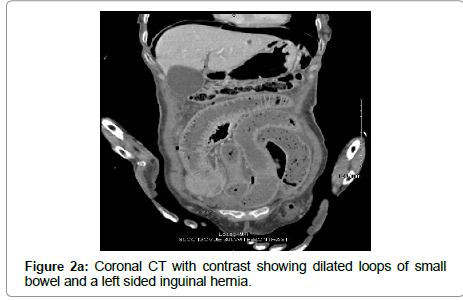

A 76 year-old hispanic lady (BMI: 19.38) with a past medical history significant for poorly controlled diabetes mellitus type II presented to the emergency department with an acute abdomen. Her pain started a week prior and was progressively worsening, which prompted her to come to the emergency department. Her last bowel movement was 4 days prior to admission without hematochezia. On admission, the patient was experiencing nausea, vomiting, chills, altered mental status, and decreased appetite. Her vitals showed a maximum temperature of 37.5°C with a heart rate of 101 beats per minute, respiration rate of 18 breaths per minute, and blood pressure was initially 57/33 mmHg which was stabilized to 118/55 mmHg after resuscitation with intravenous (IV) fluids. She was saturating at 96% on room air. Her labs showed a white blood cell count of 2.5 thousand/uL, bicarbonate of 19 mEq/L, glucose of 200 mg/dL, anion gap of 18, BUN 26 mg/dL, creatinine of 1.2 mg/dL, and lactic acid of 4.7 mMol/L. On physical exam, the patient appeared cachectic and in moderate distress. Her abdomen revealed absent bowel sounds and was distended, rigid, tympanic to percussion, and diffusely tender to palpation. Subsequent chest X-ray revealed pneumoperitoneum (Figure 1). Computed tomography (CT) scan of the abdomen and pelvis with contrast revealed small bowel proximal to the terminal ileum within the left inguinal ring (Figures 2a and 2b). Multiple loops of small bowel demonstrated decreased wall enhancement with ischemic changes. There was also a large amount of free fluid in the abdomen. We had a high suspicion for a perforated small bowel obstruction due to incarcerated and strangulated left inguinal hernia. The peritonitis led to septic shock, therefore she was stabilized with 6 L of IV normal saline, pressors, and piperacillin/tazobactam. The risks, benefits, complications, and alternatives were discussed with the patient and her family, in which they chose to proceed with surgery.